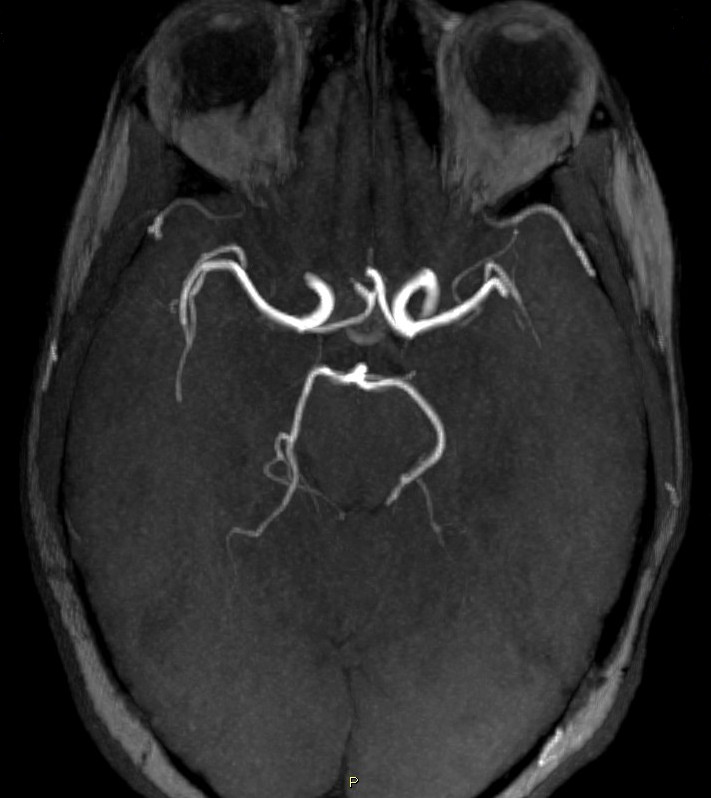

De façon physiologique, les artères communicantes postérieures ne sont pas très larges, y'a vraiment très peu de sang qui y passe (comme tu peux le voir sur ces deux angiographies) :